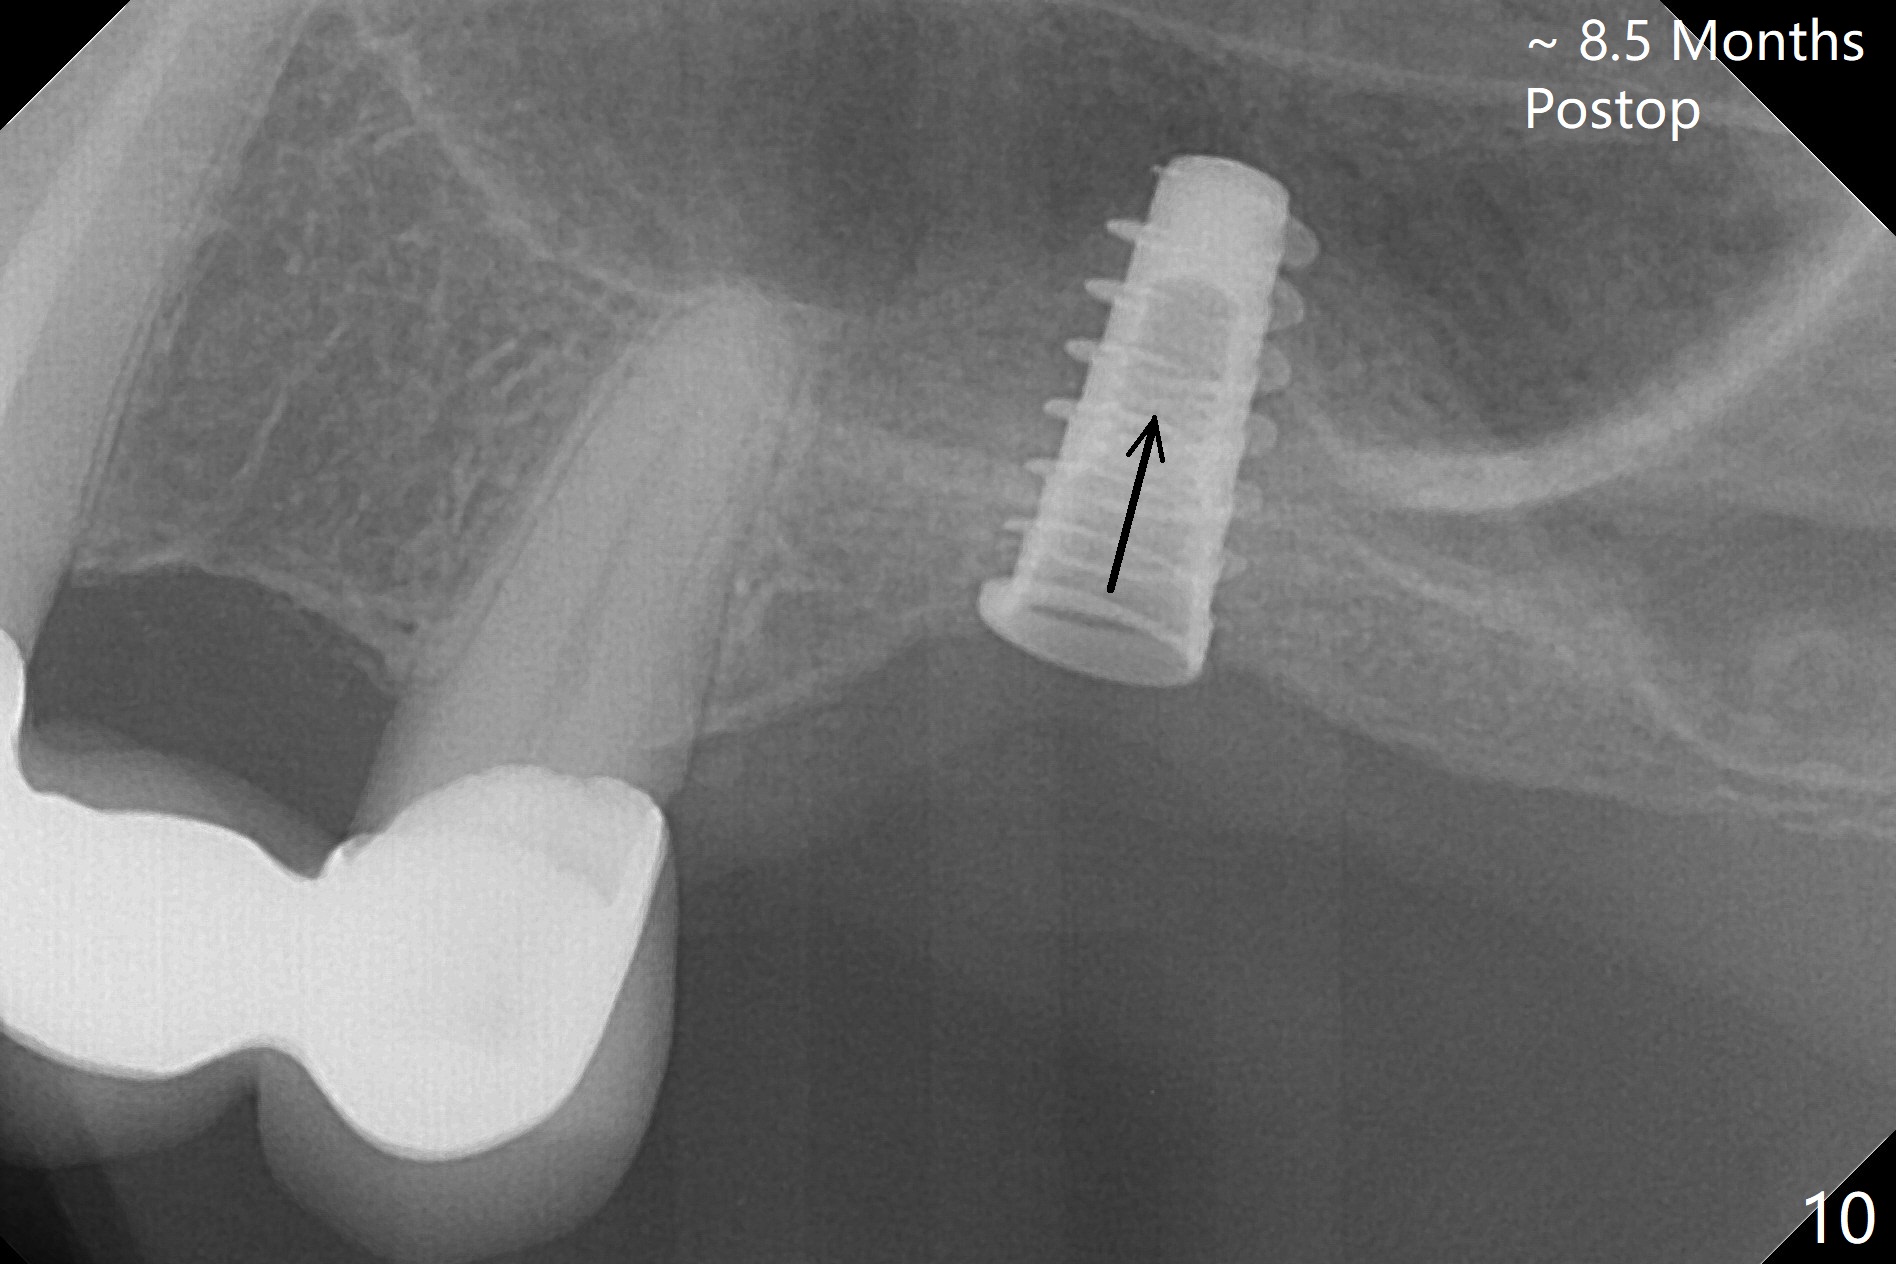

Three weeks later (approximately 8.5 months postop), the implant is found to be able to rotate when a 6.5x5.7(1) mm pair abutment is tightened with local anesthesia (there is pain associated with healing screw removal). After removal of the latter, the implant is placed deeper by hand retightening (Fig.10 arrow). Is it a better idea to use a new larger implant instead? The patient (53 years old) is scheduled to return for follow up in 3 months. In fact she returns 4 months later. The implant remains unstable and tender with loss of the crestal bone (Fig.11 *). It will be replaced with an implant (larger in diameter (5-6 mm), but shorter (7.3 mm after 5x10 mm dummy) with SLA surface after debridement and bone graft. Change the trajectory so that the coronal end will be more mesial (Fig.12 blue line). Use a healing screw and try to close the wound. In fact the patient reveals history of osteoporosis.